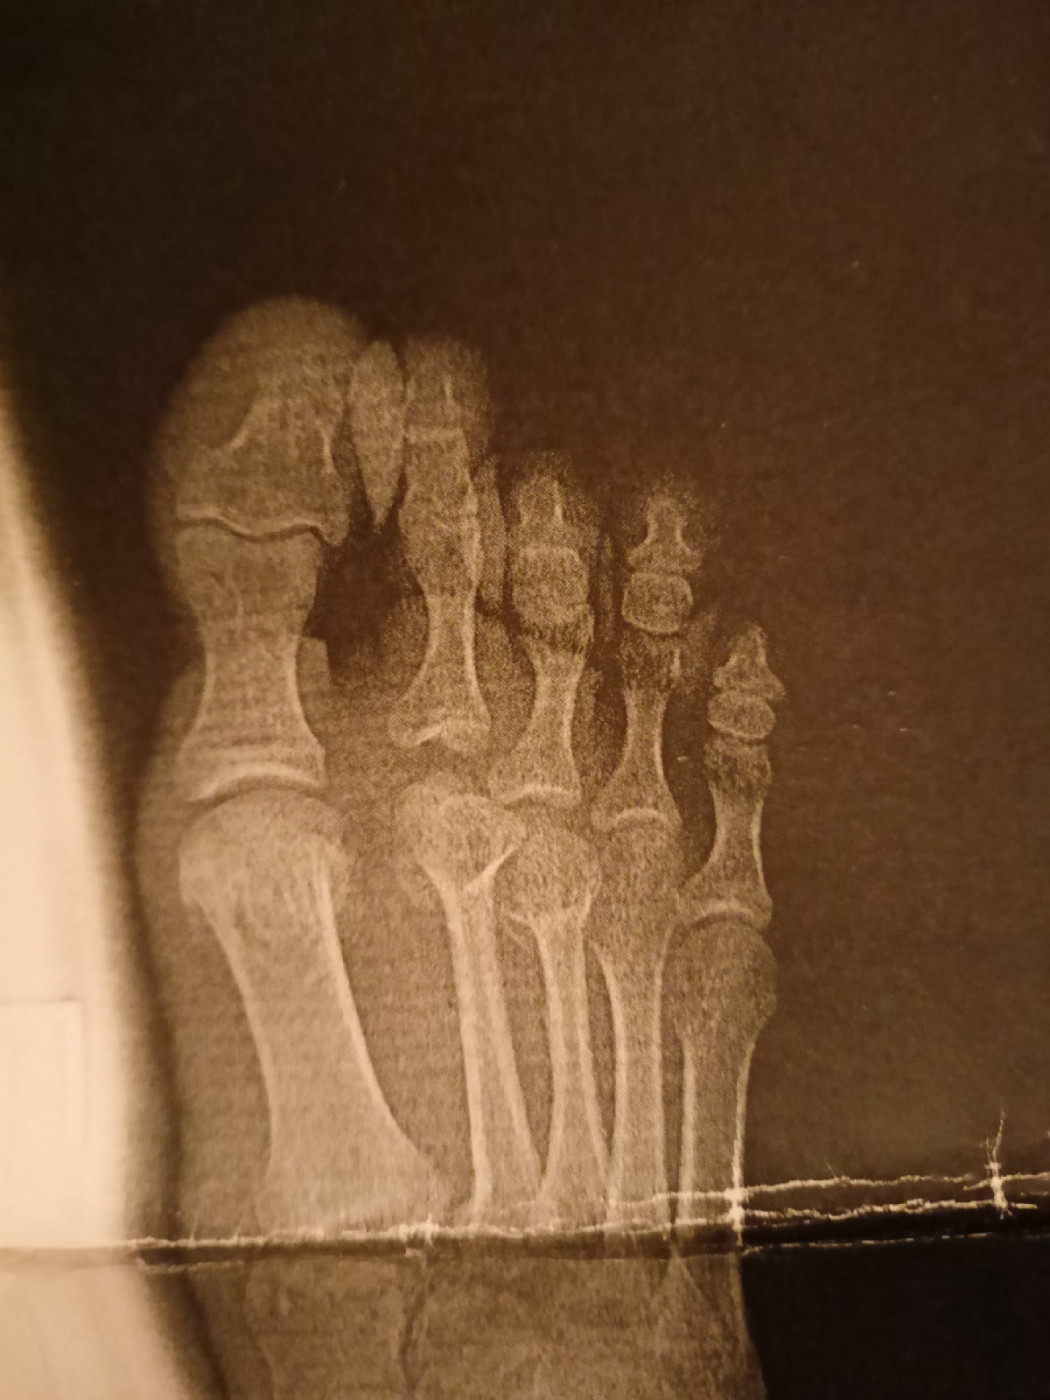

Здравствуйте, есть ли перелом?   1 ответ

Здравствуйте, есть ли перелом?